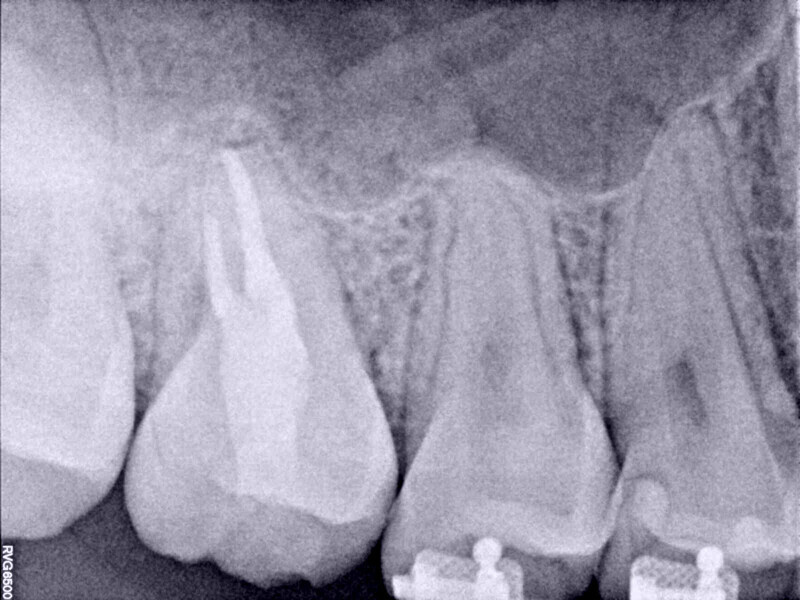

Autogenous transplantation followed by conservative root canal therapy: Three years follow-up